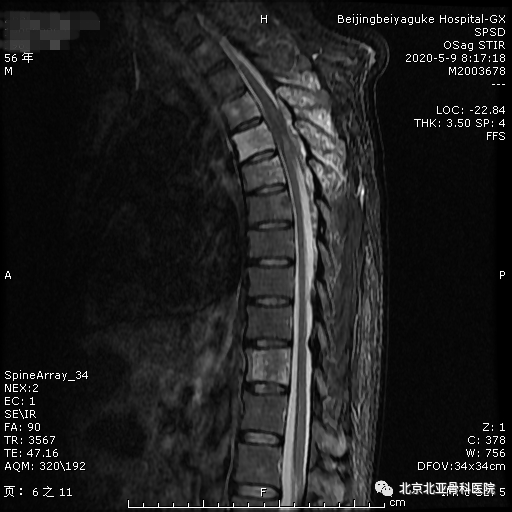

北亚脊柱科成功完成一例胃食管癌继发脊柱转移瘤切除手术!